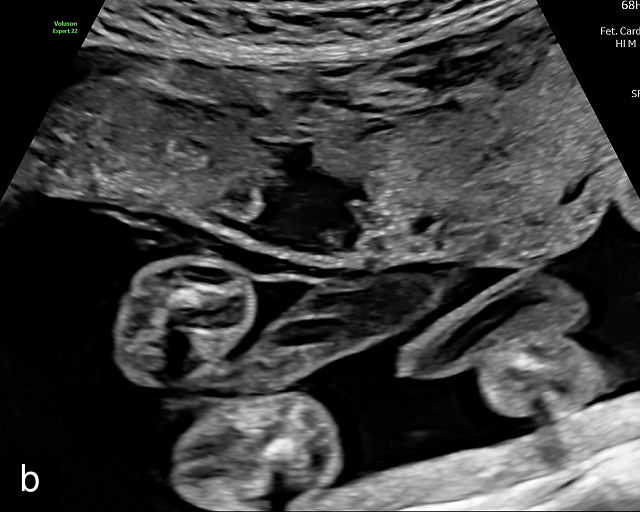

Accessory placental lobes

While most placentas consist of a single disc with several cotyledons, some placentas may have two or more separate lobes. These variations can include a bilobate placenta, where two lobes of roughly equal size are present, or a main placental body accompanied by one or more smaller accessory or succenturiate lobes (Figure 4).21,22,23,24 The cord insertions in these pregnancies are often velamentous or marginal, and blood vessels always traverse the membranes between the placental lobes. When these connecting vessels pass over the cervix, the condition is classified as Type- 2 or Type- 3 vasa previa.25,26,27,28,29,30

The sonographic features of a bilobed or succenturiate-lobed placenta include the presence of two distinct placental masses, typically one anterior and the other posterior, which may vary in size or be of equal size.21,22,23,24,26,31,32,33 These masses are connected by blood vessels, which can be visualized using color flow Doppler (Figure 4).28

It is crucial to confirm that the masses are truly separate and not connected as part of a single lateral placenta, which may be mistaken for a bilobate placenta. Additionally, careful scanning should verify that both masses share similar echogenicity to distinguish true placental tissue from other structures such as subchorionic hematomas, myometrial contractions or uterine fibroids, which can mimic accessory lobes. Prominent placental lakes may also be observed between the lobes.23,26

The placental cord insertion in these cases is often velamentous and may be located between the placental lobes (Figure 4b; Video 2). In rare cases, furcate insertion, in which the cord vessels branch before reaching the placental tissue, between the lobes has been reported.24

Pregnancies conceived via assisted reproductive techniques, particularly in-vitro fertilization, are at increased risk of developing placentas with accessory lobes.22 Bilobate placentas have also been linked to an elevated risk of pre-eclampsia, though risks for small-for-gestational-age infants and preterm birth were not significantly increased.22

In most cases, pregnancies with accessory lobes have favorable outcomes in the absence of vasa previa. However, because accessory lobes are strongly associated with vasa previa, transvaginal ultrasound with color Doppler imaging is recommended whenever they are identified.3,4,25,28,34,35,36